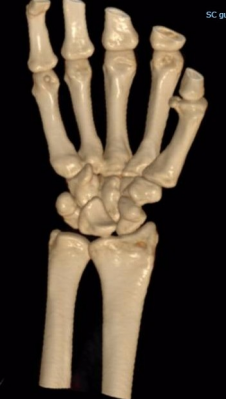

术后第一天,患者意识恢复清醒,复查头部CT提示颅内血肿清除彻底。全腹CT、双腕关节CT显示:肠管管壁明显水肿增厚,邻近肠系膜肿胀,肠间隙模糊,盆腔少量积液,腹腔内未见游离积气,提示肠管或肠系膜损伤;右侧月骨脱位,左侧桡骨远端骨折。

胃肠小儿外科、脊柱创伤外科会诊讨论,确定了分期治疗方案。术后第2天,胃肠小儿外科张达主任医师在全麻下为患者行小肠破裂修补术+腹腔脓肿清除术+肠粘连松解术+肠排列术。脊柱创伤外科薛建康主任医师为患者行左侧桡骨骨质手法复位后石膏外固定,后行右月骨脱位切开复位。

(月骨脱位) (固定术后)